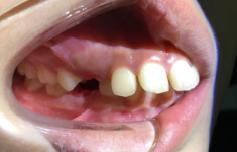

❶ 个别前牙反牙合:此类错牙合可使下颌前伸运动受限。

前

后

❷ 前牙反牙合:此类错牙合影响下颌前伸,影响上颌发育。